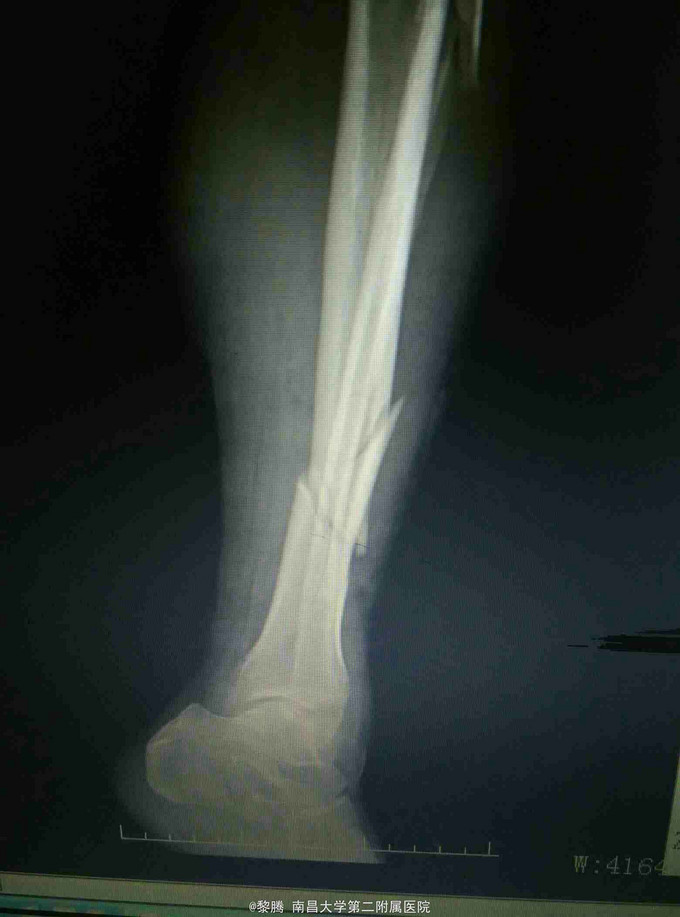

车祸致左小腿肿痛,活动受限8小时 患者中年女性,因车祸致左小腿疼痛、肿胀,伤后当即出现左小腿活动受限,余无特殊不适,急诊入院,行左胫腓骨正侧位片提示左胫腓骨骨折。

查体:左小腿肿胀明显,局部皮肤可见皮下瘀血,左小腿远端压痛明显,可及骨擦感,膝关节主动活动受限,被动活动无明显异常,踝关节主被动活动受限,左足背动脉搏动存在,肢体无明显感觉异常。 辅查:左胫腓骨正侧位片提示左胫腓骨骨折

诊断:左胫腓骨骨折 治疗:胫骨骨折复位内固定